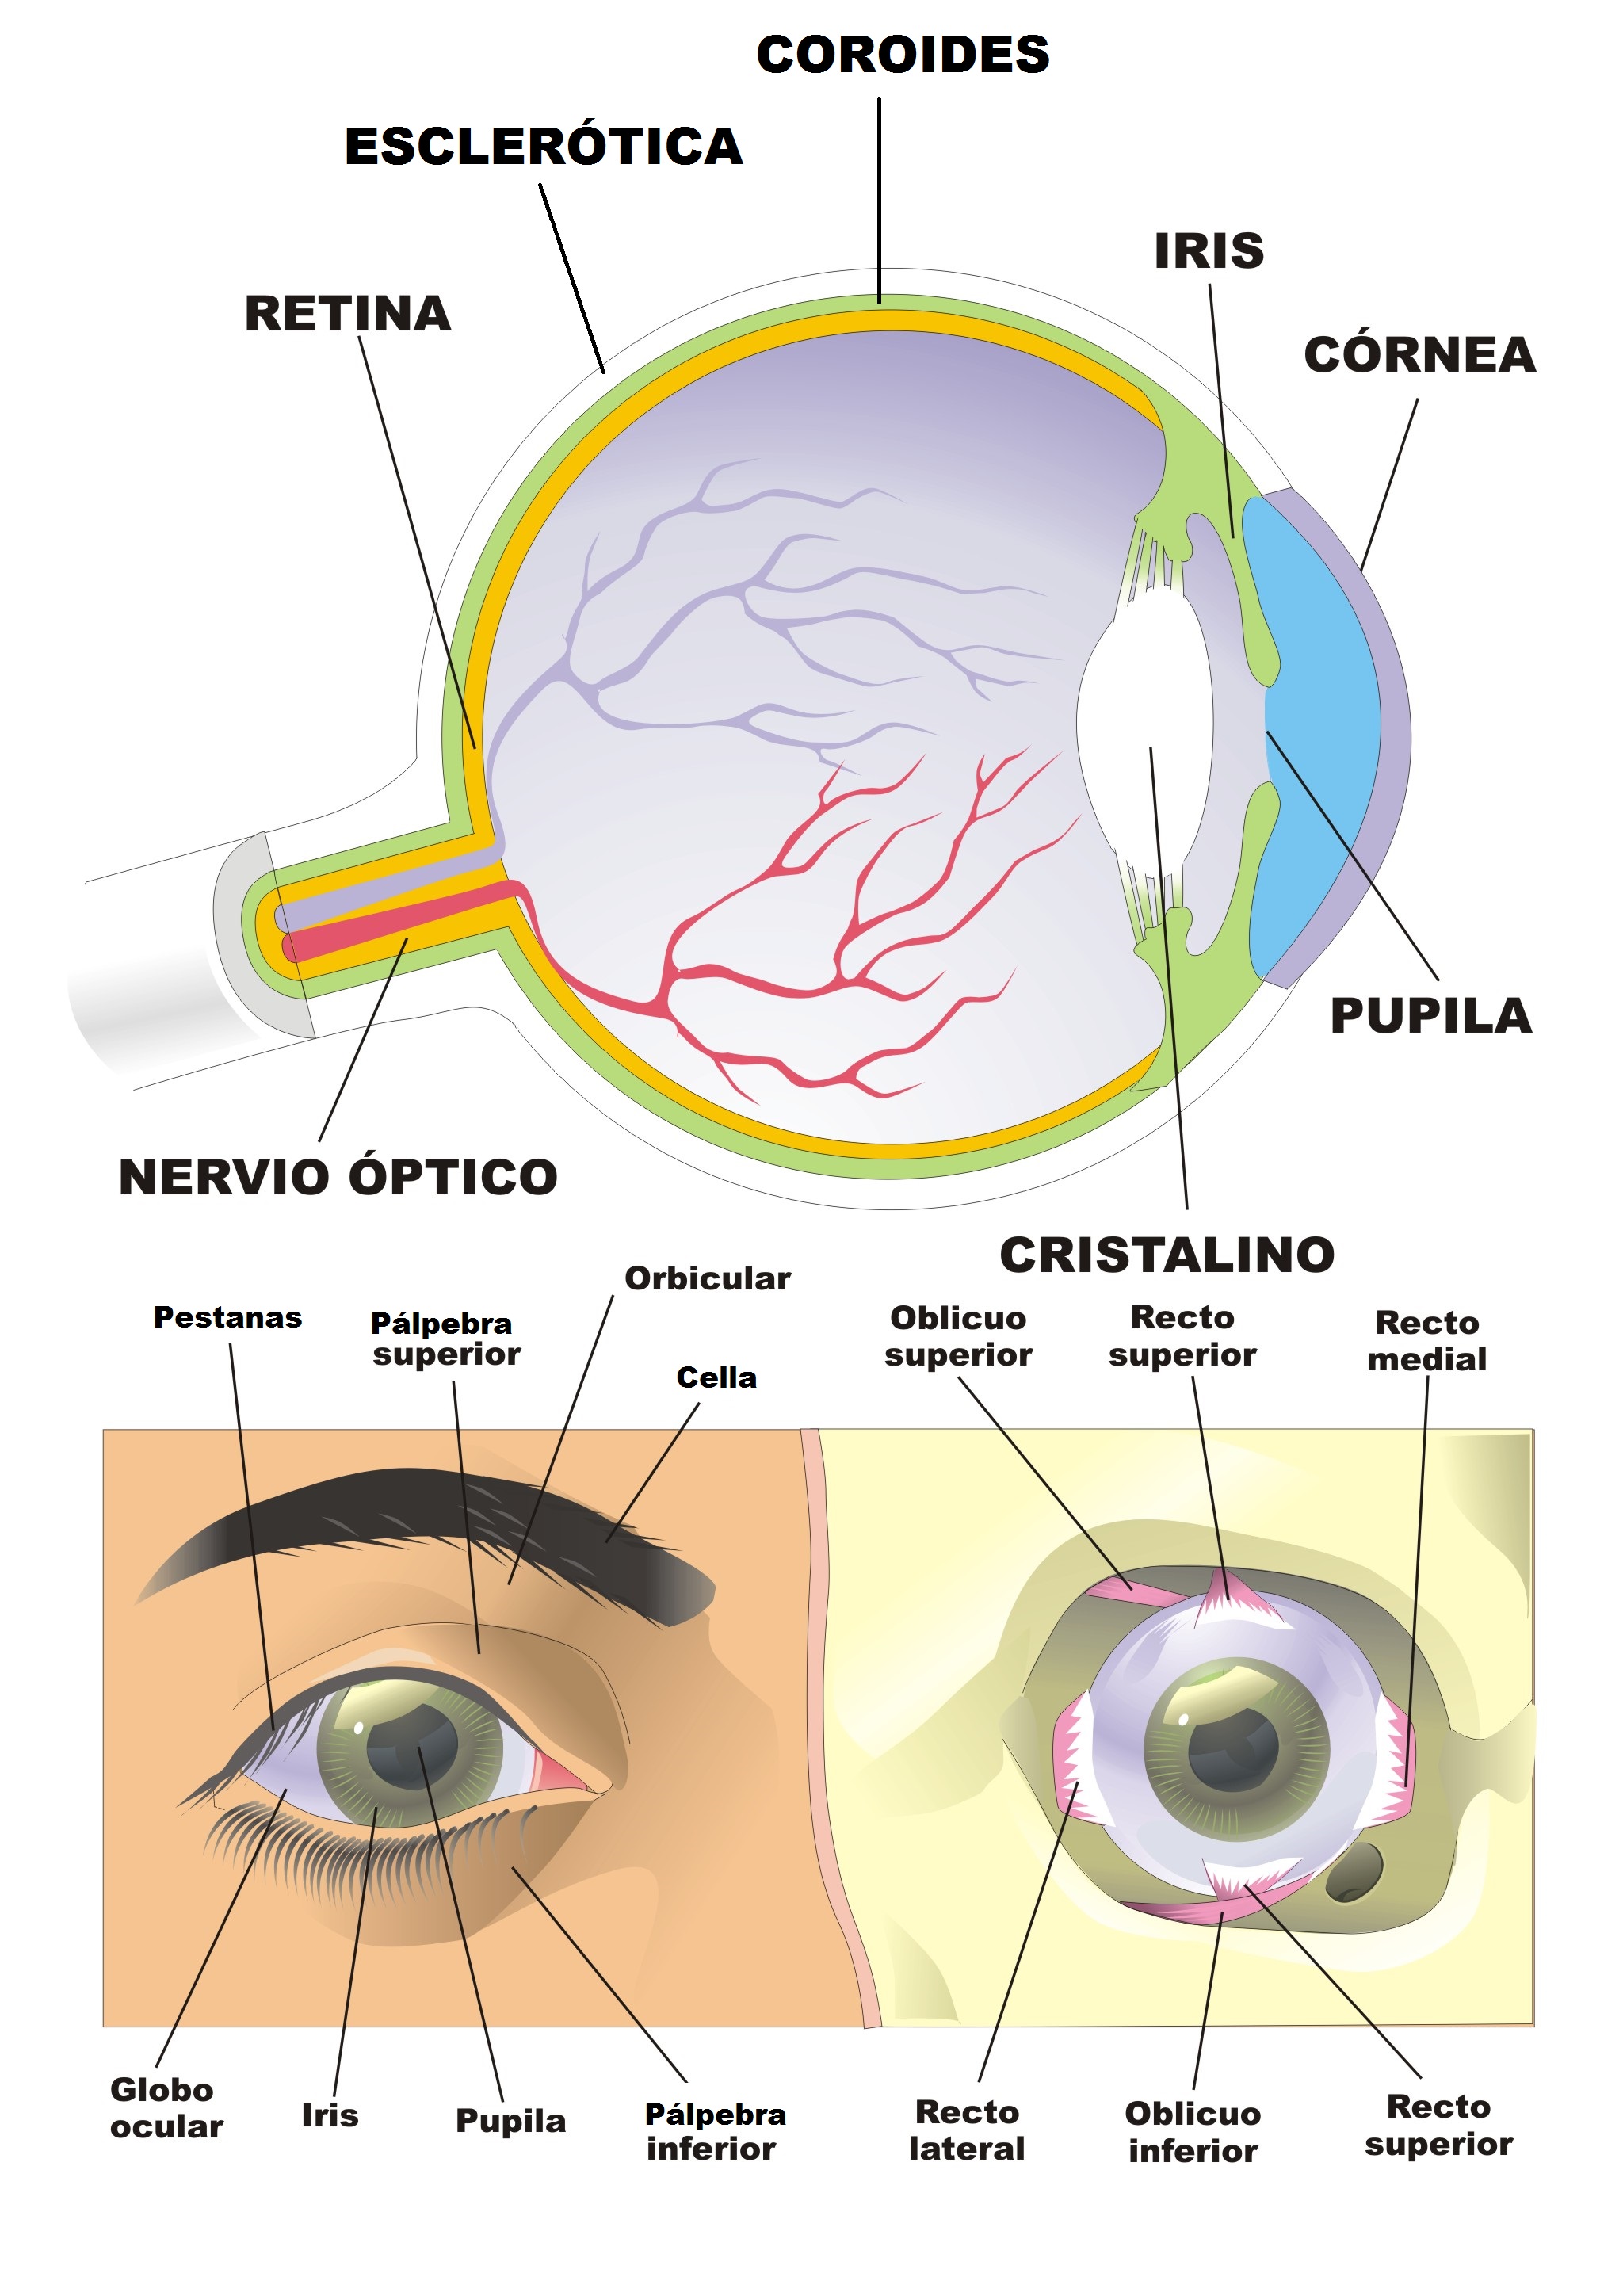

Anatomía do ollo

O ollo é o órgano encargado da visión; está formado polo globo ocular e as estruturas anexas:

- Estruturas anexas:

o Pálpebras: pel que protexe o globo ocular do exceso de luz ou de posibles lesións.

o Pestanas: pelos situadas nos bordos das pálpebras para evitar a entrada de substancias estrañas.

o Glándula lacrimal: secreta líquido para manter o ollo hidratado e limpalo de partículas de po.

- Globo ocular:

o A esclerótica: parte externa que rodea ao ollo; é unha capa dura e resistente que dá soporte ao globo ocular e remata na córnea.

o A córnea: membrana transparente situada na parte anterior do ollo, diante do iris. Permite a formación da imaxe na retina, actuando como unha lente converxente e desviando a luz cara ao cristalino.

o O iris: é a parte coloreada do ollo. Ten forma anular deixando no centro un oco chamado pupila por onde entra luz ao ollo.

o A pupila: o iris ábrese e péchase, modificando o tamaño da pupila e controlando a cantidade de luz.

o O cristalino: é unha lente biconvexa transparente encargada de enfocar as imaxes.

o O humor acuoso: líquido transparente que está entre a córnea e o cristalino.

o O humor vítreo: líquido viscoso entre a retina e o cristalino que dá consistencia ao globo ocular.

o A retina: é a capa máis interna do ollo e a que recibe a luz. Nela hai neuronas que reciben o impulso nervioso e o transportan ao cerebro. Existen dous tipos de receptores para a luz:

§ Os conos: detectan as cores

§ Os bastóns: detectan a intensidade luminosa

Como funciona?

O ollo humano ten forma de globo (globo ocular) e está rodeado por unha membrana resistente, a esclerótica. A luz penetra a través da córnea (protexida polas pálpebras). O iris regula a cantidade de luz que pasa pola pupila. O cristalino (lente) forma a imaxe na retina (fina membrana onde se atopan as células receptoras, conos, que captan as cores, e bastóns, que captan a luz). As sensacións luminosas recibidas na retina son enviadas ao cerebro polo nervio óptico. Aínda que o obxecto estea máis ou menos lonxe de nós, conseguimos velo nitidamente grazas aos músculos ciliares que permiten a acomodación do ollo, é dicir, que o cristalino modifique a súa curvatura para que a imaxe se forme sempre na retina.